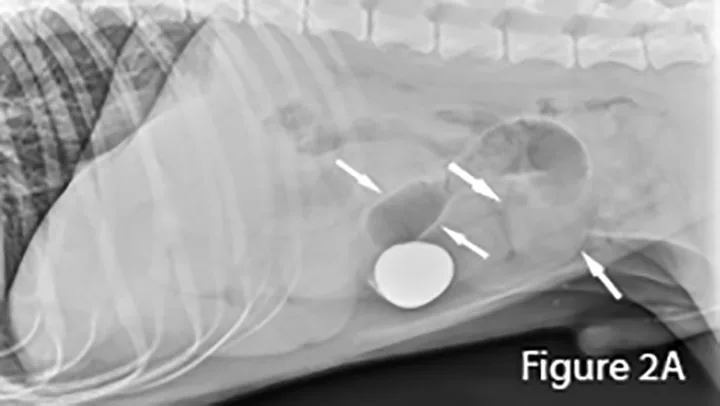

2. Foreign Body Small Intestinal Obstructions

A foreign body (ie, rock) is identifiable in this canine small intestine. The markedly dilated segment of jejunum (arrows) leading up to the foreign body (~4× the height of L5) is significant.